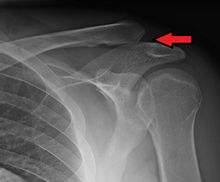

| A Separated Shoulder XRay modified to easily show bones. Notice the separation between the end of the collarbone and the scapula. | |

A separated shoulder (also known as acromioclavicular separation, AC separation), is a common injury to the acromioclavicular joint. It is a joint dislocation, but it is not called a dislocated shoulder, as that term refers to a glenohumeral joint (shoulder joint) dislocation. The AC joint is located at the distal end of the clavicle, known as the acromial end, and attaches to the acromion of the scapula. Although this is part of the shoulder, a dislocated shoulder and a separated shoulder are completely different. Acromioclavicular separation occurs as a result of a downward force being applied to the superior part of the acromion, either by something striking the top of the acromion or by falling directly on it. The injury is more likely to occur if the shoulder is struck with the hand outstretched. Despite the scapula pulling on the clavicle during impact, the clavicle remains in its general fixed position because of the sternoclavicular joint ligaments.

Diagnosis is based on physical examination and an x-ray. A separated shoulder occurs because of a direct blow to the AC joint or a fall on the elbow that forces the head of the humerus into the AC joint. Furthermore, AC separation can be identified point tenderness, pain at the AC joint with cross-arm adduction, and pain relief with an injection of a local anesthetic. The cross-arm adduction will produce pain specifically at the AC joint and will be done by elevating the arm to a 90° angle, flexing the elbow to a 90° angle, and adducting the arm across the chest. The pain in the shoulder is hard to pinpoint of the innervation of the AC joint and the glenohumeral joint. An injury to the AC joint will result in pain over the AC joint, in the anterolateral neck and in the region in the anterolateral deltoid.